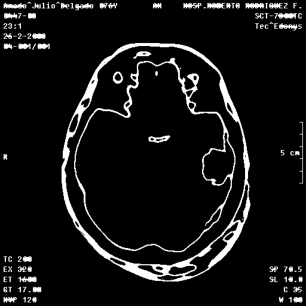

An example of an applications of our proposed strategy to a medical image is shown in Figure 7. In this case, we used different values of and in the . This is a preliminary result. A deeper paper about these results will be published.